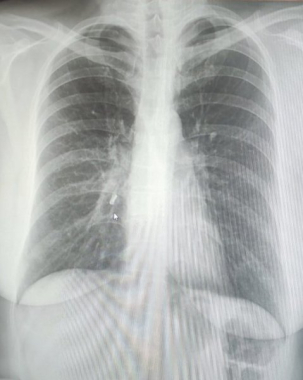

Молода жінка звернулася зі скаргами до пульмонолога амбулаторно-поліклінічного відділення. Вона розповіла медикам, що у неї постійний виснажливий кашель спостерігається з липня 2022 року.

Такий стан тривав у неї вісім місяців. Ліки, які вона приймала, ніяк позитивно на ситуацію не вплинули.

Медики з'ясували, що частина зуба опинилася у легенях під час пологів, які відбувалися шляхом кесаревого розтину. Під час екстреної процедури він відколовся.